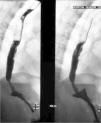

Exploraciones complementariasEn los estudios complementarios destacaba: unos linfocitos CD4 17 células/mm3, carga viral 2.600 copias/ml y antigenemia de citomegalovirus negativa. La tomografía axial computarizada de cuello mostraba pequeñas adenopatías laterocervicales bilaterales, sin observarse masas en los espacios parafaríngeos. Un esofagograma realizado tras un intento fallido de endoscopia demostró la presencia de una úlcera en el tercio distal del esófago (fig. 2).